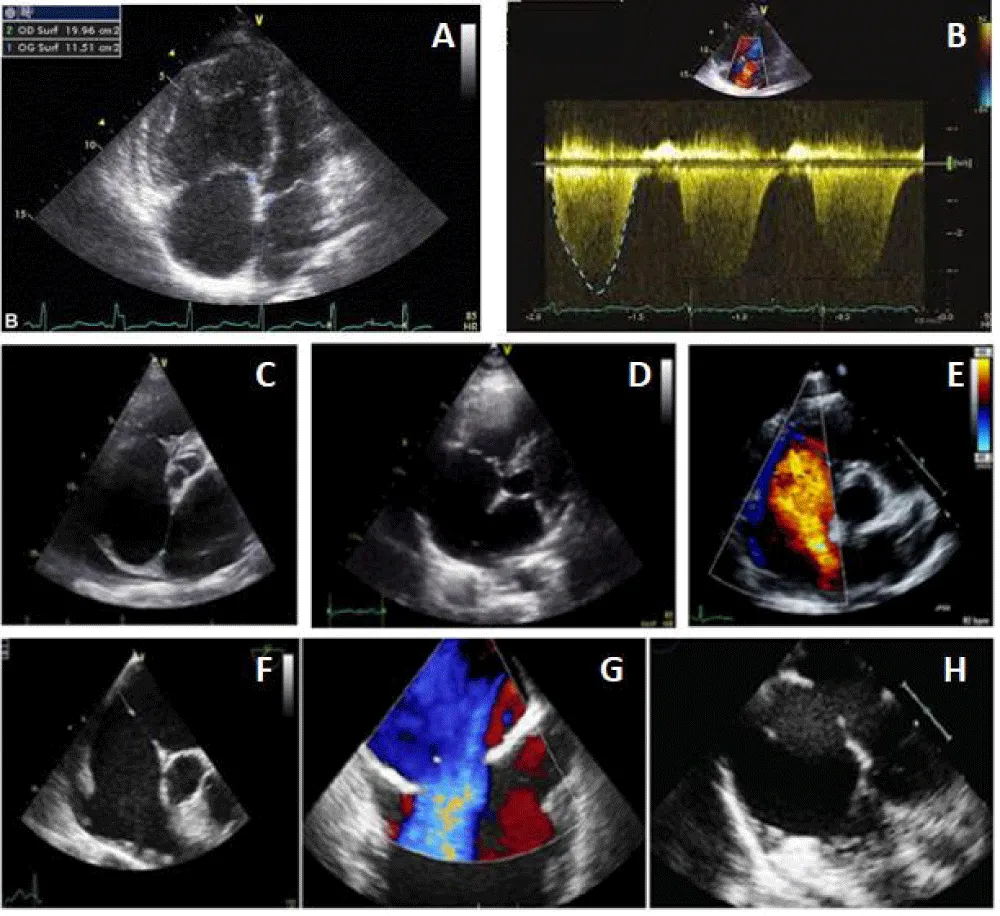

After confirming the correct positioning of the prosthesis and the absence of conflict with the mitral valve, the pulmonary veins, and the superior vena cava, we released successfully the Occluder by anti-clockwise rotation of its rod (Figure 4).

Figure 4: Procedure TTE.